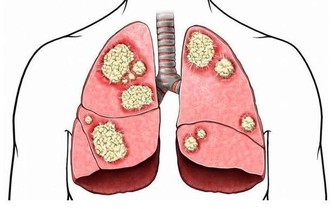

為什麼會得痛風

痛風,是因為人體內血液中的尿酸水平過高導致的,是尿酸鹽沉積在組織內引起的疾病。體內尿酸水平升高,主要有兩大原因,

第一就是體內產生了太多的尿酸;

第二就是排出體外的尿酸太少。

尿酸又是嘌呤代謝的產物,而人體內的嘌呤除了自身產生的之外,很重要的一個來源就是通過食物攝取。所以,如果排除了自身體質後,患痛風就要考慮平時的飲食是不是出現了問題。